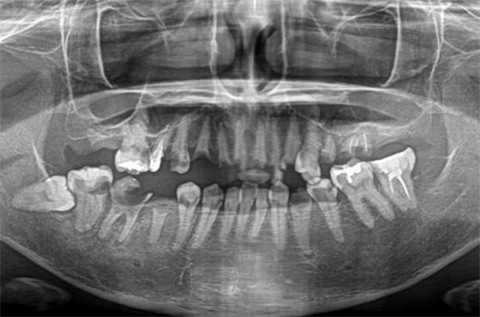

施行名 : 審美歯科(虫歯などをインプラント体によって改善する施術)

副作用やリスク : 麻酔で腫れやむくみを生じる場合があります。

また、劣化や口内の手入れを怠ることにより脱落する場合があります。

施術の価格:8万〜90万(税抜き)

※個人差があり、効果を保障するものではありません